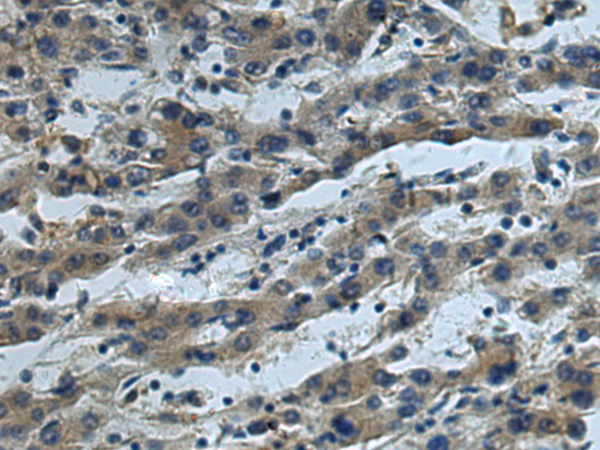

IHC positive control: |

Human tonsil and Human liver cancer |

IHC Recommend dilution: |

50-200 |